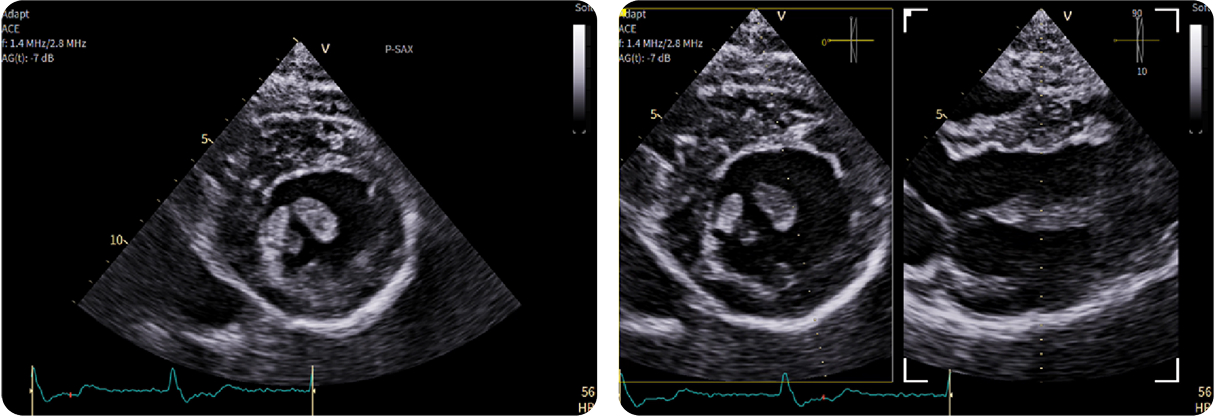

Dentro l'immagine

There is a world outside the stent mesh

Caso condiviso da Saima Mushtaq

Paziente con anamnesi di malattia coronarica e pregresso impianto di stent sulla discendente anteriore sinistra.

Per prima cosa, esamina l'intera scansione. Concentrati sul tronco comune e sulla porzione prossimale della discendente anteriore sinistra.

Fifty shades of grey

Caso condiviso da Marcello De Santis